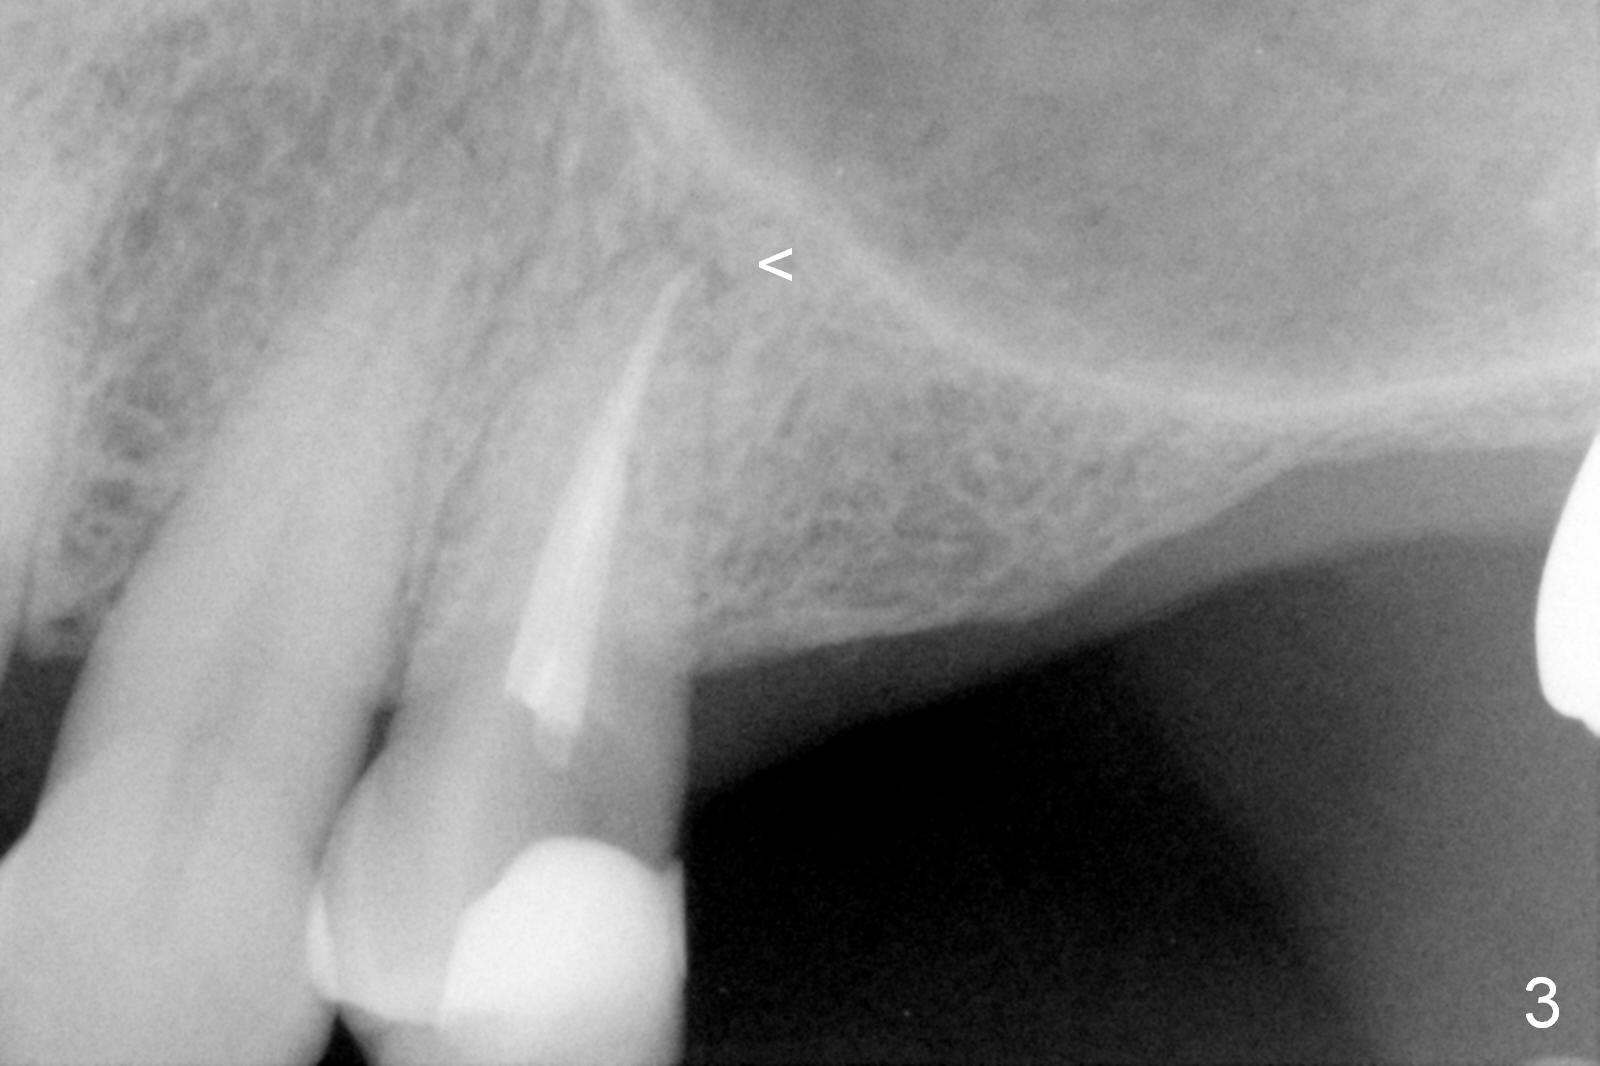

A 64-year-old man (MM) had caries at the tooth #12 (Fig.1), requiring root canal therapy (RCT, Fig.2). One year later, the periapical radiolucency reduces (Fig.3 <, as compared to that in Fig.2). The tooth remains asymptomatic 7 years posts RCT (Fig.4). A year later, the tooth has pain and buccal gingival swelling (probing tenderness); periradicular radiolucency is evident (Fig.5 arrowheads). It appears that the root fractures. Between the 7th and 8th years post RCT, the patient masticated mainly on the left side, while implants were placed at #30 and 31. The patient plans to have 4 implants in the upper left sextant (Fig.6). While implants are being placed at the site of #12 (Clindamycin) and 13, sinus lift seems mandatory at the sites of #13 and (initial depth will be 5-6 mm). By the time implants to be placed at #14 and #15, the bone height may increase.